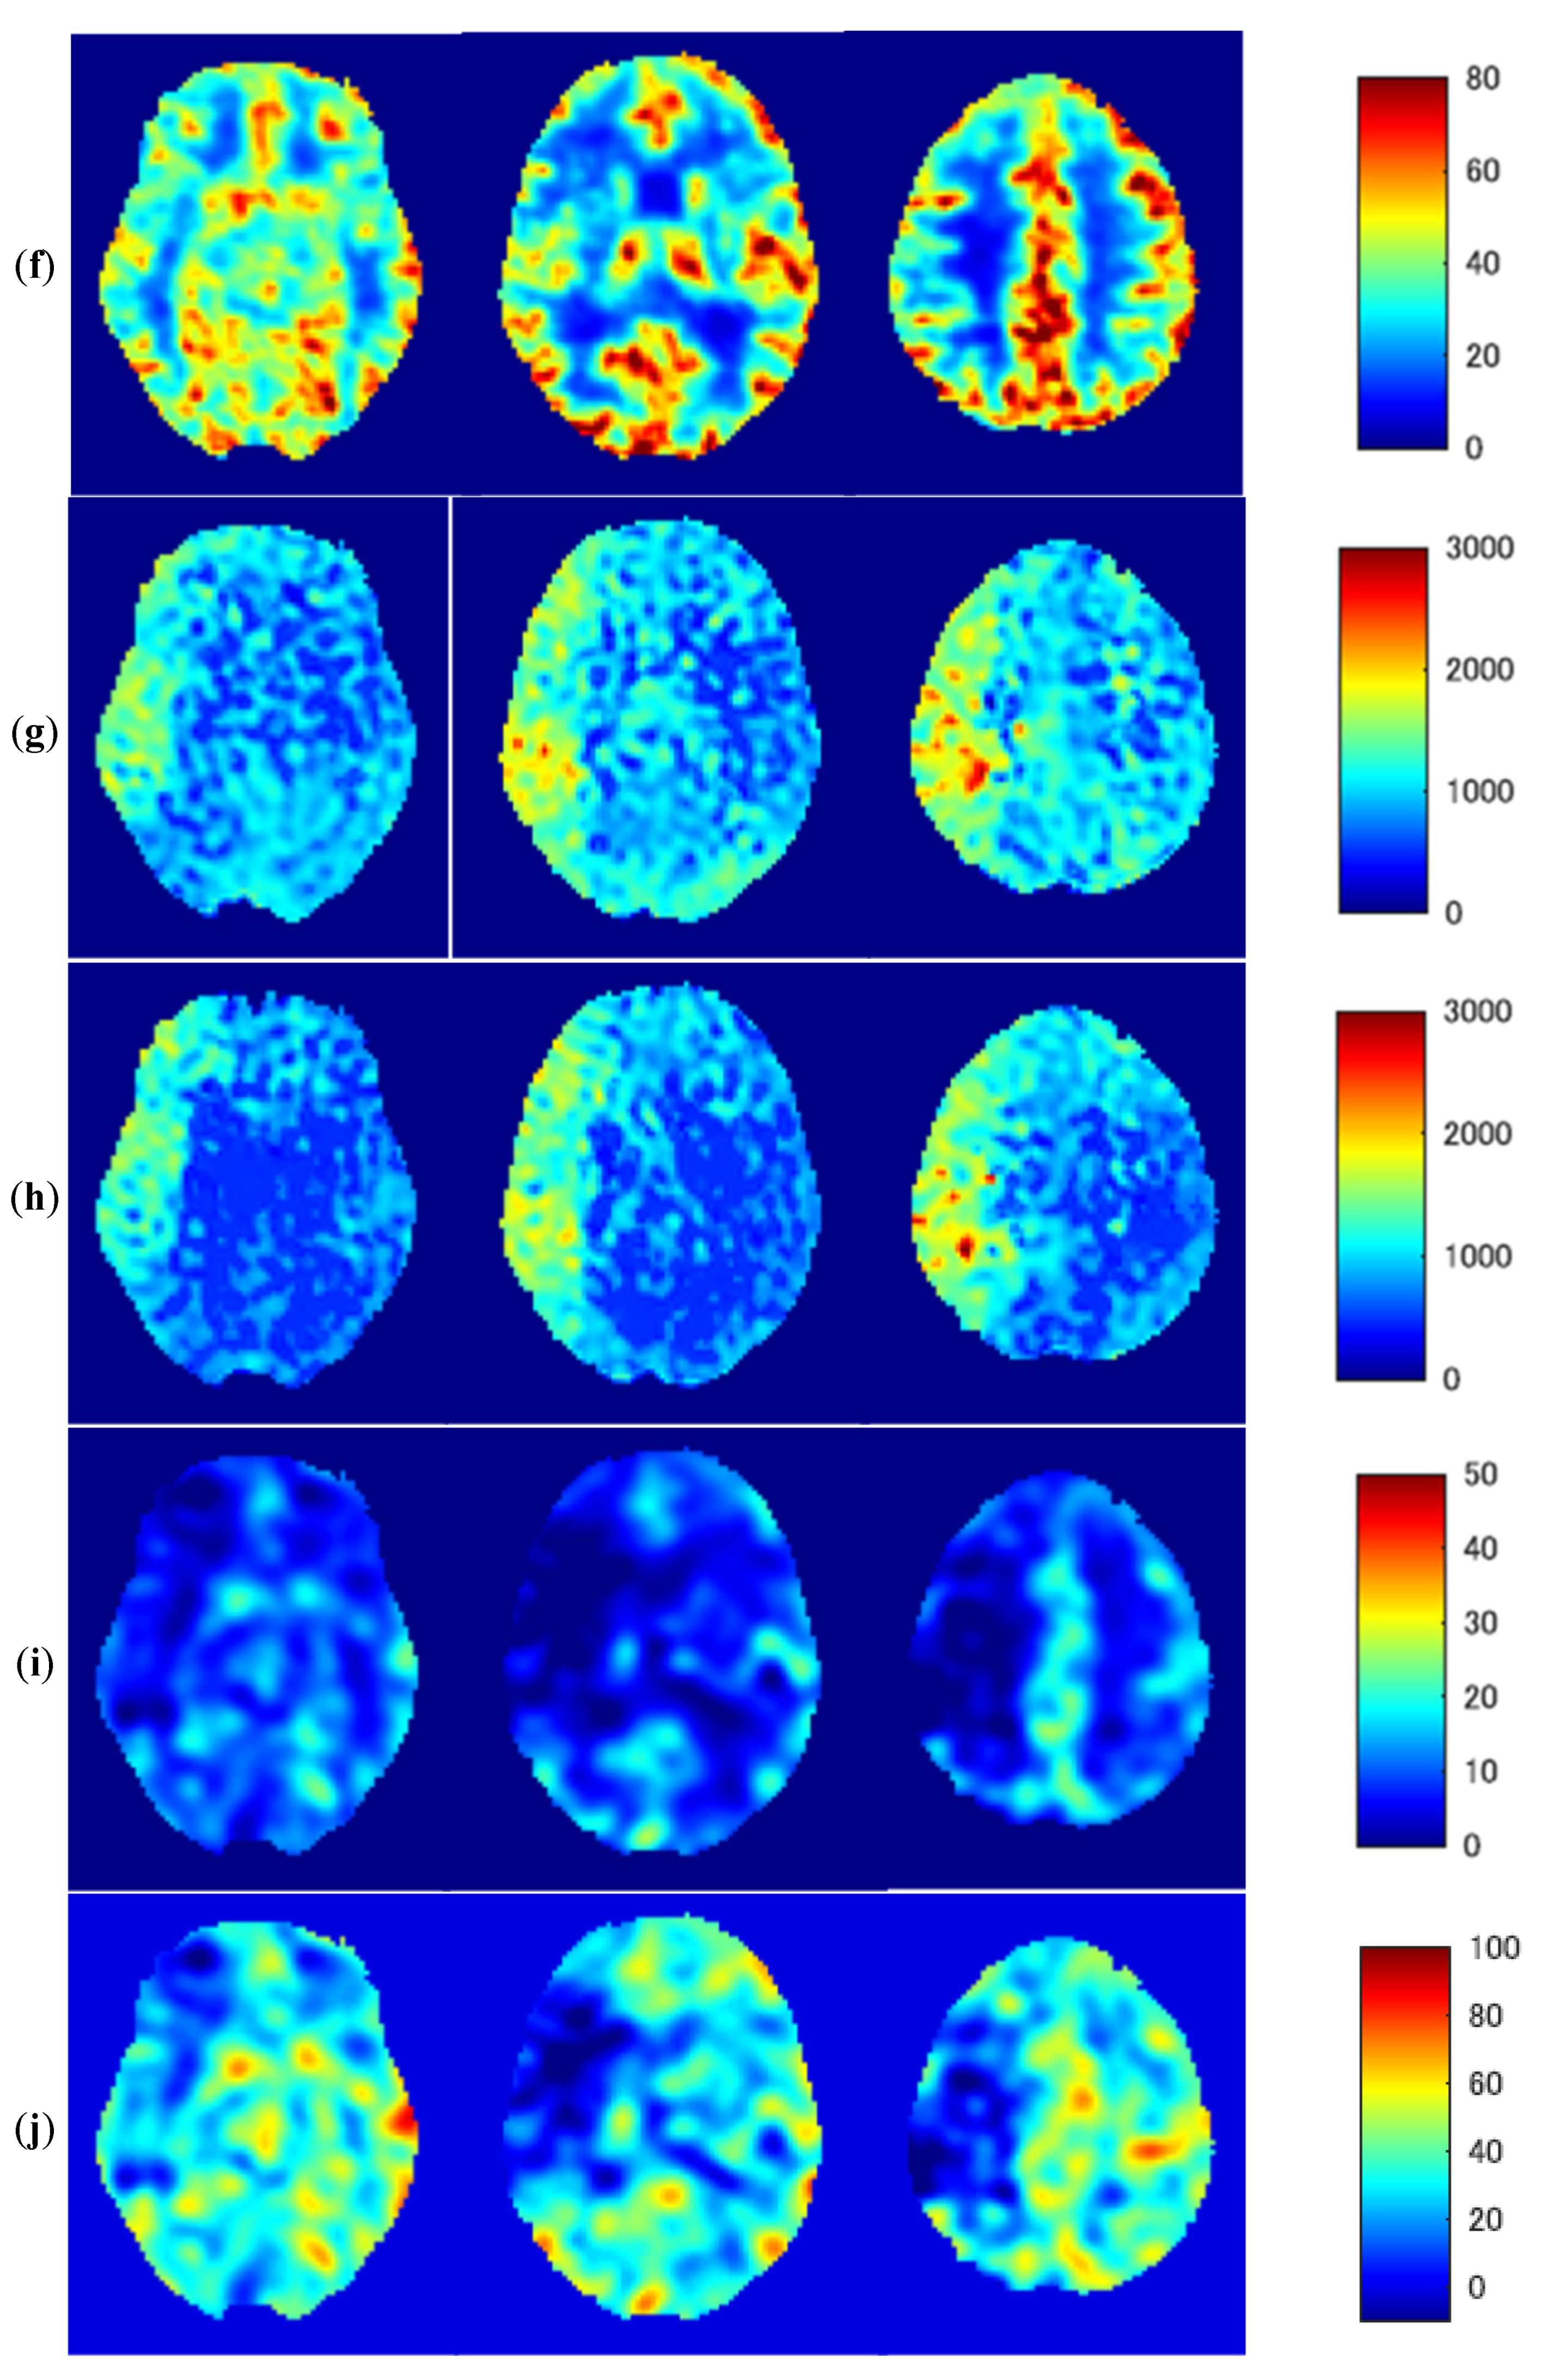

3.3. Representative Images

Figure 5 shows representative images of a 46-year-old woman with severe MMD (patient No. 6) with transient ischemic attack (TIA) symptoms. A T2-weighted MR image (a) shows no abnormal findings in the brain parenchyma; however, MR angiography (b) demonstrates severe stenosis of the right ICA. Despite the slight overestimation of ASL-CBF compared with PET-CBF, baseline and post-ACZ ASL-CBF with ATT correction (c,d) are similar to baseline and post-ACZ PET-CBF (e,f), respectively. Baseline ASL-ATT was prolonged in the right MCA territory (g). Although the prolonged ASL-ATT in the right MCA territory remained about the same even after ACZ loading, post-ACZ ASL-ATT was shortened in the left MCA territory due to the decreased vascular resistance (h). Decreases in ΔPET-CBF and PET-CVR in the right MCA territory (i,j, respectively) were similar to a negative/positive inversion of prolonged ASL-ATT.

Figure 5.

Representative images of a 46-year-old woman with severe Moyamoya disease (patient No. 6). T2-weighted MR image (a), MR angiography (b), baseline ASL-CBF (c), post-ACZ ASL-CBF (d), baseline PET-CBF (e), post-ACZ PET/CBF (f), baseline ASL-ATT (g), post-ACZ ASL-ATT (h), ΔPET-CBF (i), and CVR (j) CVR; cerebrovascular reactivity.